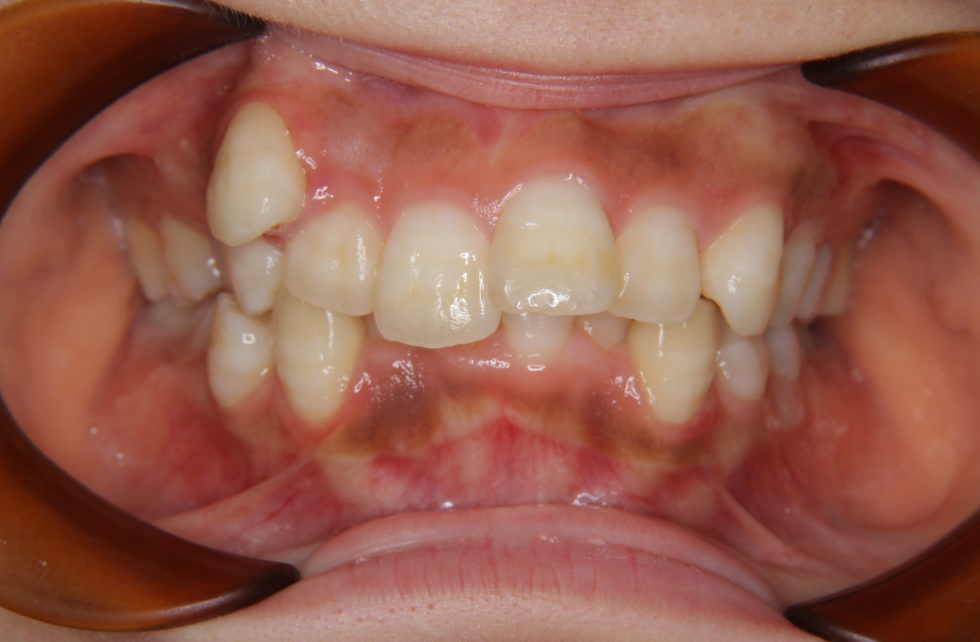

初診時年齢20歳の女性 上顎右側犬歯の低位唇側転位を主訴として来院された。

上顎右側犬歯は完全に歯列から外れて生え、また、左側中切歯は約7㎜突出していた。下顎前歯にも著しい叢生があった。セファロ分析の結果、著しい叢生を伴う骨格性上顎前突と診断し上下顎小臼歯を抜歯していただき、矯正用アンカースクリューを併用し、マルチブラケット装置を使用して動的治療を行った。矯正用ゴムなどの使用状況も良く良好な結果が得られた。歯の痛みはあったが2、3日で普通の食事ができるため過度な心配は必要がない。また、歯が動いていることが目に見えて分かるためモチベーションが保てたとおっしゃっていた。

動的治療期間2年0カ月(調整来院20回)